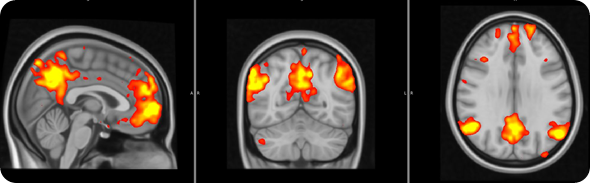

Fibro brain 1 - resized

In order to address this question, we used a brain imaging technique called ‘functional Magnetic Resonance Imaging’, which allows us to examine how brain activity changes in association with certain states or tasks.

In this study brain activity was investigated when the participants received painful stimuli, as well as when they received visual cues informing the subjects of impending pain onset (pain anticipation) and pain offset (relief anticipation).

We saw that the healthy subjects showed large brain responses, in many regions, when they were anticipating pain or relief. Some of these changes are likely to be due to the detection of ‘salient’ event. In other words, some of these responses may be non pain-specific and may simply reflect the fact that the subjects were detecting an ‘interesting event’.

However, other responses would seem to be even more interesting, and possibly pain specific: for instance the healthy volunteers activated a region called the ‘periaqueductal gray region’, which we know exerts a modulatory effect on the pain signals coming to the periphery (this is a region that if stimulated electrically can alleviate pain).

The healthy volunteers also showed that a region involved in the processing of ‘reward’/’punishment’, the so called ventral tegmental area (VTA), was activated during pain anticipation, and deactivated during relief anticipation.